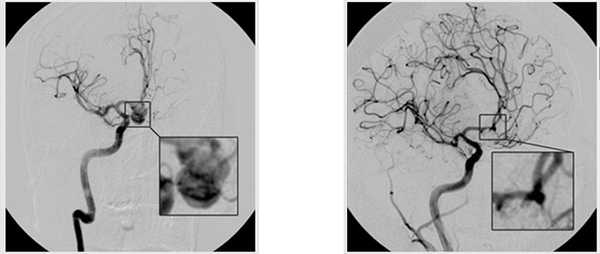

Представляю вниманию фото 2 аневризм — основной артерии и развилки средней мозговой артерии, с которыми пришлось столкнуться в нашей клинике за последние 2 недели.

Мешотчатая аневризма развилки основной артерии

Мешотчатая аневризма развилки левой средней мозговой артерии. Аневризма и ветви М2 обведены шариковой ручкой.

Аневризму развилки основной артерии пришлось перевести в другое ЛПУ для эндоваскулярного выключения (заполнения спиралями), а аневризма СМА была оперирована в нашей клинике.